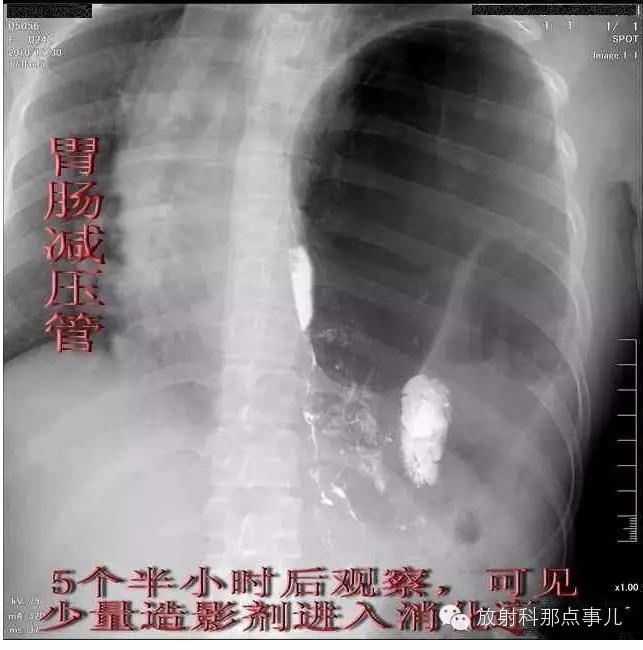

门诊腹部透视发现左侧胸腔巨大气液平面,为排除膈疝口服钡剂,但造影剂未见进入胃内。嘱住院,外科给予胃肠减压、补液等处理常规处理(未引流出明显气、液体)。5个半小时后再次检查,见少量造影剂进入消化道;为进一步了解情况,予泛影葡胺分别经胃管推注及口服,但均未进入胃内。当天进行外科急诊手术。

更正:检查时间在左上方。